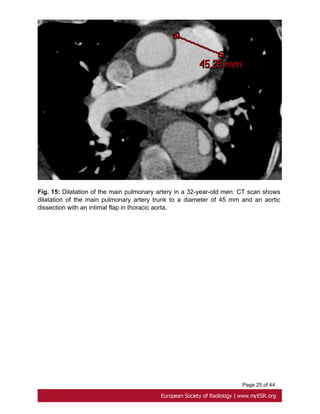

A less common cardiovascular manifestation of Marfan syndrome is dilatation of the main

pulmonary artery. The upper values have been established at 24 mm at the pulmonary

artery bifurcation and 34mm at the pulmonary artery root[23]. Fig. 15 on page 24

Fig. 15: Dilatation of the main pulmonary artery in a 32-year-old men. CT scan shows

dilatation of the main pulmonary artery trunk to a diameter of 45 mm and an aortic

dissection with an intimal flap in thoracic aorta.

Page 25 of44 Fig. 15: Dilatation of the main pulmonary artery in a 32-year-old men. CT scan shows dilatation of the main pulmonary artery trunk to a diameter of 45 mm and an aortic dissection with an intimal flap in thoracic aorta.